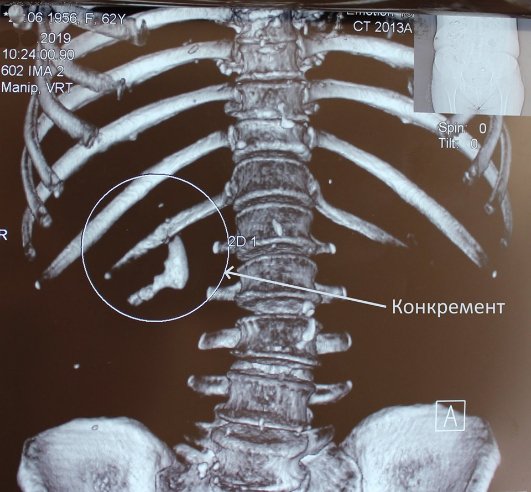

Зазначили, що «найцікавішим» випадком було видалення великого кораловидного конкременту (каменя, – ред.). Він займав всю ниркову миску і нижню чашку.

Команда урологів успішно провела черезшкірне дроблення та видалила камінь повністю.